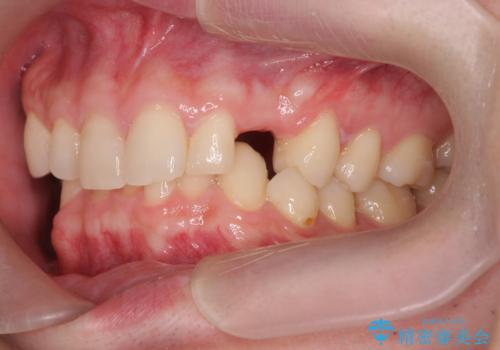

前歯に目立たないノンクラスプデンチャーを作りたい

- 目立つ前歯の欠損の状況を改善されたい、と希望され来院されました。

歯を削らず、インプラント治療でもない方法を希望されたのでバネの目立たないノンクラスプデンチャーを製作します。